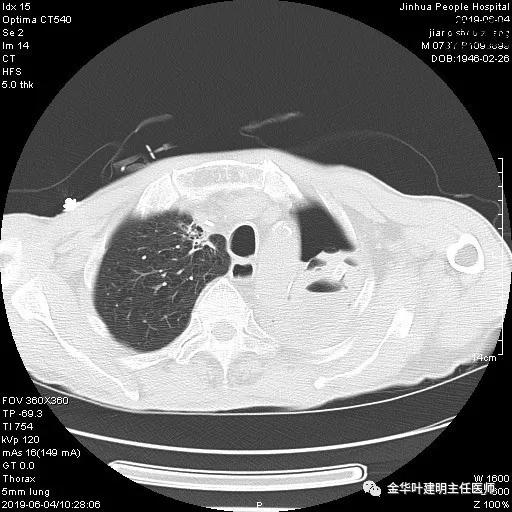

6.4上午:24小时引流出血性乳糜液1800毫升。是否再次手术进行右进胸胸导管结扎,抑或继续保守治疗非常纠结!压力非常大!!多方讨论会诊无法取得一致意见,但一般认为,引流量在1000毫升以上宜积极手术。情况与浙二医院范军强教授联系,请求指导,范教授认为左侧肺手术,损伤胸导管主干的机会较小,多数可保守治疗而愈。在他们的病例中,也有结扎胸导管后引流量仍无减少,效果并不能完全保证。建议可以考虑胸管夹管观察(因为淋巴管压力低,予以适当的压力,漏出量可能会明显减少),同时继续禁食,并静脉营养支持,引流管口可能会有渗液,注意更换敷料。与家属充分沟通后决定试夹管;这天血色素9.0 g/L;胸部CT复查示: